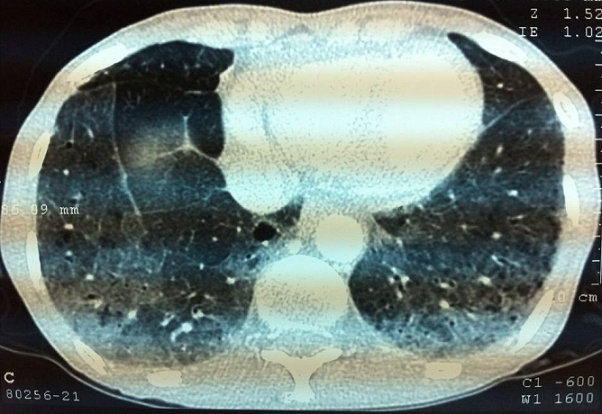

Le lupus érythémateux systémique (LES) est une connectivite qui se traduit le plus souvent par une atteinte multiviscérale, il est associé à des manifestations pleuropulmonaires dans plus de 50% des cas. Néanmoins, la pneumopathie interstitielle diffuse (PID) reste une atteinte rare et elle n'est qu'exceptionnellement révélatrice. Patiente âgée de 49 ans, hospitalisée pour exploration d'adénopathies inguinales avec dyspnée d'effort stade II (classification NYHA). L'examen trouvait une patiente en bon état général, eupnéique au repos, des adénopathies jugulo-carotidiennes infracentimétriques bilatérales et des adénopathies inguinales bilatérales. À l'auscultation pulmonaire on notait des râles sous crépitants au niveau des 2 bases pulmonaires. A la biologie il y avait une anémie normochrome normocytaire à 9,8g/dl d'hémoglobine, une lymphopénie à 480/mm3 et un syndrome inflammatoire biologique. Le bilan phosphocalcique sanguin et urinaire était normal. La TDM thoraco-abdomino-pelvienne montrait des adénomégalies cervico-thoraco-abdominales, un épanchement péricardique de faible abondance et une PID dont l'aspect évoque une pneumopathie infiltrante lymphocytaire . Le bilan immunologique trouvait des anticorps antinucléaires positifs à 1/3200 et des anticorps anti-DNA natifs positifs. Le diagnostic de LES avec atteinte pulmonaire (PID) a été retenu devant: la péricardite, la lymphopénie, les anticorps antinucléaires et anticorps anti-DNA natifs positifs. Les étiologies des PID subaigües ou chroniques sont dominées par la sarcoïdose, la fibrose pulmonaire idiopathique et les fibroses pulmonaires associées aux connectivites (sclérodermie, syndrome de gougerot sjogren...). Une exploration fonctionnelle respiratoire faite avant l'instauration du traitement était normale et une corticothérapie a été instaurée à la dose de 1mg/kg/j avec une évolution clinique favorable.